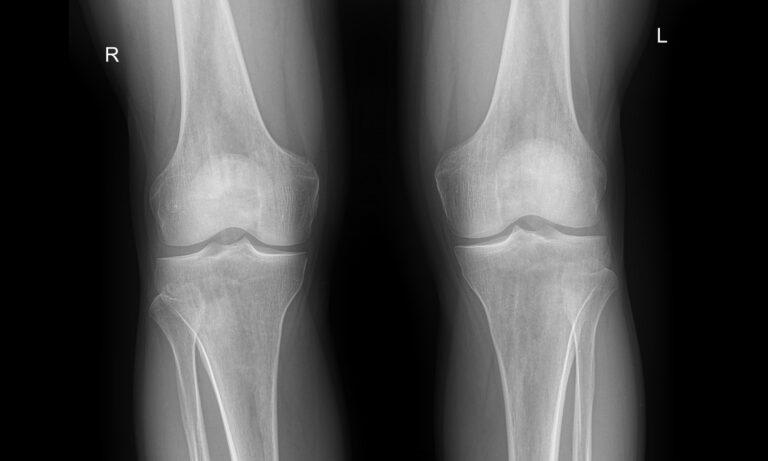

Назад Рентген обоих коленных суставов

Коленные суставы ежедневно выполняют большое количество движений, связанных с ходьбой, бегом, прыжками, приседаниями и подъемом, и выдерживают вес человека, каким бы он ни был. Как и любые другие суставы в теле, они подвержены воспалению и другим патологическим изменениям, а также травмам, инфекциям, новообразованиям и возрастным дегенеративным процессам. Это одни из самых крупных суставов в теле человека.

Первым видом диагностики пациентов с ортопедическими патологиями обычно является рентген. Это простое, быстрое, неинвазивное и безболезненное обследование с высоким уровнем информативности. В большинстве случаев его бывает достаточно для постановки диагноза и выбора тактики лечения. Кроме того, уровень облучения, который получают обследуемые, минимален благодаря современной цифровой аппаратуре.

Что покажет рентген обоих коленных суставов в одной проекции

В протоколе у каждого сустава описывается:

• Состояние мягких тканей;

• Суставная щель ― в норме, расширена, сужена, затемнена, имеет дополнительные включения;

• Состояние суставных  поверхностей и их соответствие друг другу ― несоответствие говорит о вывихе;

• Положение надколенника ― обычное или нет;

• Состояние костной ткани и надкостницы ― могут быть обнаружены участки разрежения, размягчения или других патологических процессов, а также свежие и сросшиеся переломы.